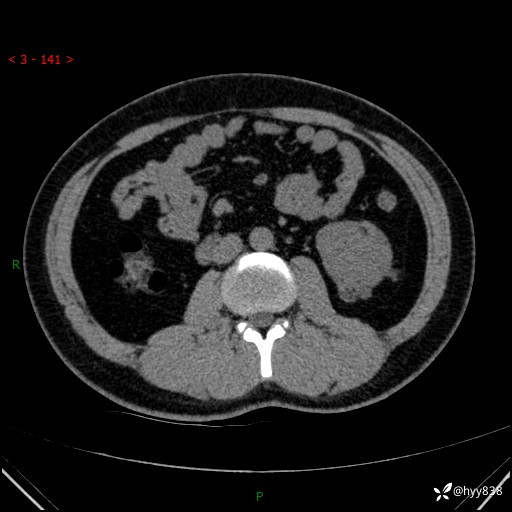

患者性别:男

患者年龄:28岁

简要病史:右肾肿瘤术后,常规复查

辅助检查:CT

临床诊断:右肾肿瘤术后

腹部CT+颅脑CT平扫